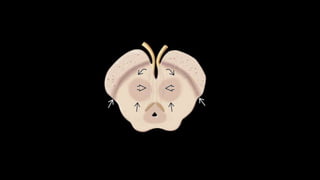

• Gânglios da base

• Sistema neuronal complexo

• Integração e execução motora, cognitiva, emocional e funcional;

• Sistema dopaminérgico estriatonigral

• Encontrado ao longo do cérebro, predominantemente no mesencéfalo

• Formado por:

• Gânglios da base: Núcleo caudado, putamen e globo pálido

• Substância nigra

• Núcleo subtalâmico

Substância nigra

Pars reticularis

Pars compacta